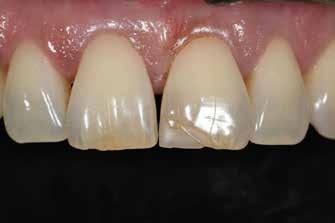

ezen a területen, a fogászat profitál az ilyen fejlesztésekből, és ma már számos kezelési megoldást kínálunk pácienseinknek. Rezidens korom alatt klinikai szakfelügyelőként dolgoztam akadémiai környezetben, ahol elsősorban kivehető fogpótlásra szoruló geriátriai betegeket kezeltem, valamint olyanokat, akiknek fix fogpótlásra, például fog- vagy implantátummal ellátott hagyományos rögzített fogpótlásra (azaz korona és híd) volt szükségük, elsősorban arany vagy fémkerámia felhasználásával. Az ezekben az években megfigyelt klinikai kudarcok és a beavatkozások invazív jellege, nevezetesen a foghúzásra vonatkozó több fúrás és egyszerűbb döntések jelentős szerepet játszottak a kutatási irányvonalam kialakításában az évek során. Ez volt az az időszak is, amikor elkezdtem többet foglalkozni az adhezív fogászattal, ami megváltoztatta a protetikai fogászat klasszikus arculatát, és határozottan kevésbé invazívvá tette azt (1. a-d ábrák). Ma, az intenzív transzlációs és klinikai kutatás eredményeként, különös tekintettel a fogászati bioanyagok alkalmazására, klinikai szakértelmem a minimálisan invazív, adhezív eljárások alkalmazására összpontosít a protetikai fogászatban, a szövődmények kezelésére és a költséghatékony kezelési lehetőségek felkínálására.

1. a-d ábrák: a) Fogerózió a molárisok okkluzális felszínén, b) maratás foszforsavval, c) minimálisan invazív műgyanta-kompozit fedőréteg levegővel történő felszívása, d) adhezív ragasztott fedőréteg a hiányzó zománc és dentin helyreállítására.